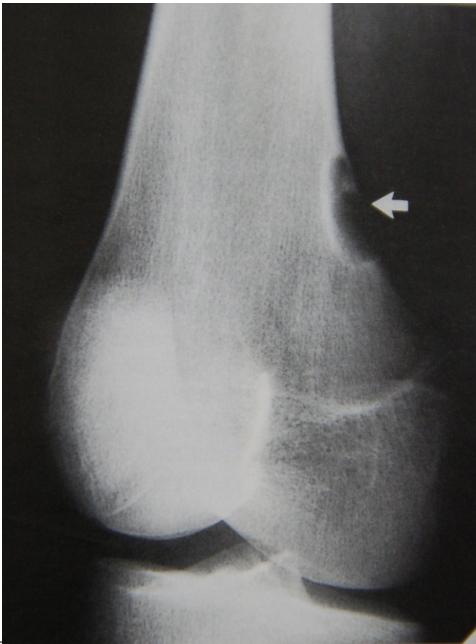

Epiphyseal-Metaphyseal Lesions

Benign aggressive lesions:

- Giant Cell Tumor (GCT)

- Aneurysmal Bone Cyst (ABC)

- Osteoblastoma

Giant Cell Tumor

Aneurysmal Bone Cyst